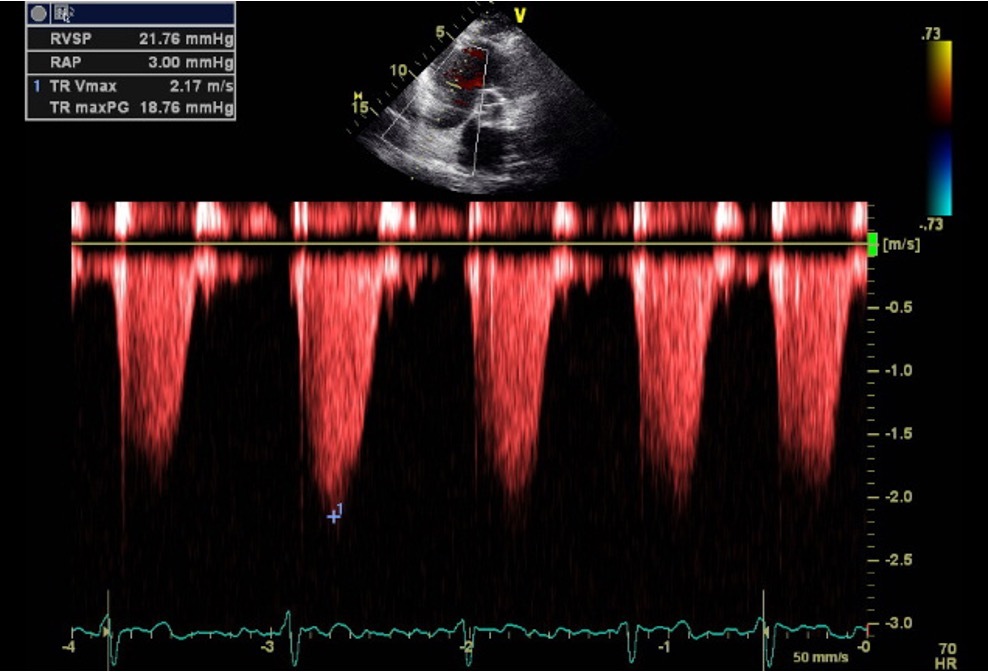

9

Q

Should we measure the the TR?

A

Yes because we can see the peak